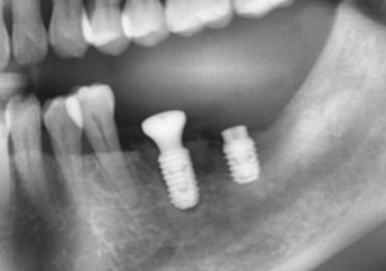

2023. 10

약 2개월의 회복 기간을 갖고, 2차 수술 및 보철과정을 진행하였습니다.

과정은 구강스캐너인 "3Shape Trios 4"를 이용하여 진행되었고,

아래와 같이 치료는 잘 마무리 되었습니다.

대표원장인 제가 직접 디자인하고 설계한 "서지컬 가이드"를 토대로,

수술은 매우 안전하게 진행되었고, 부족한 부위에는 추가로 골이식을 진행하였습니다.